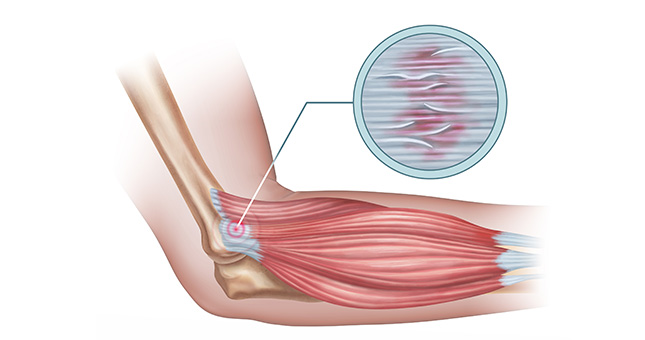

Tendinosis

La tendinosis es un proceso patológico como consecuencia de la degeneración de las fibras musculares que conforman el tendón lo que da lugar a la aparición del dolor y, en ocasiones, a la pérdida de movilidad. (No existe inflamación)